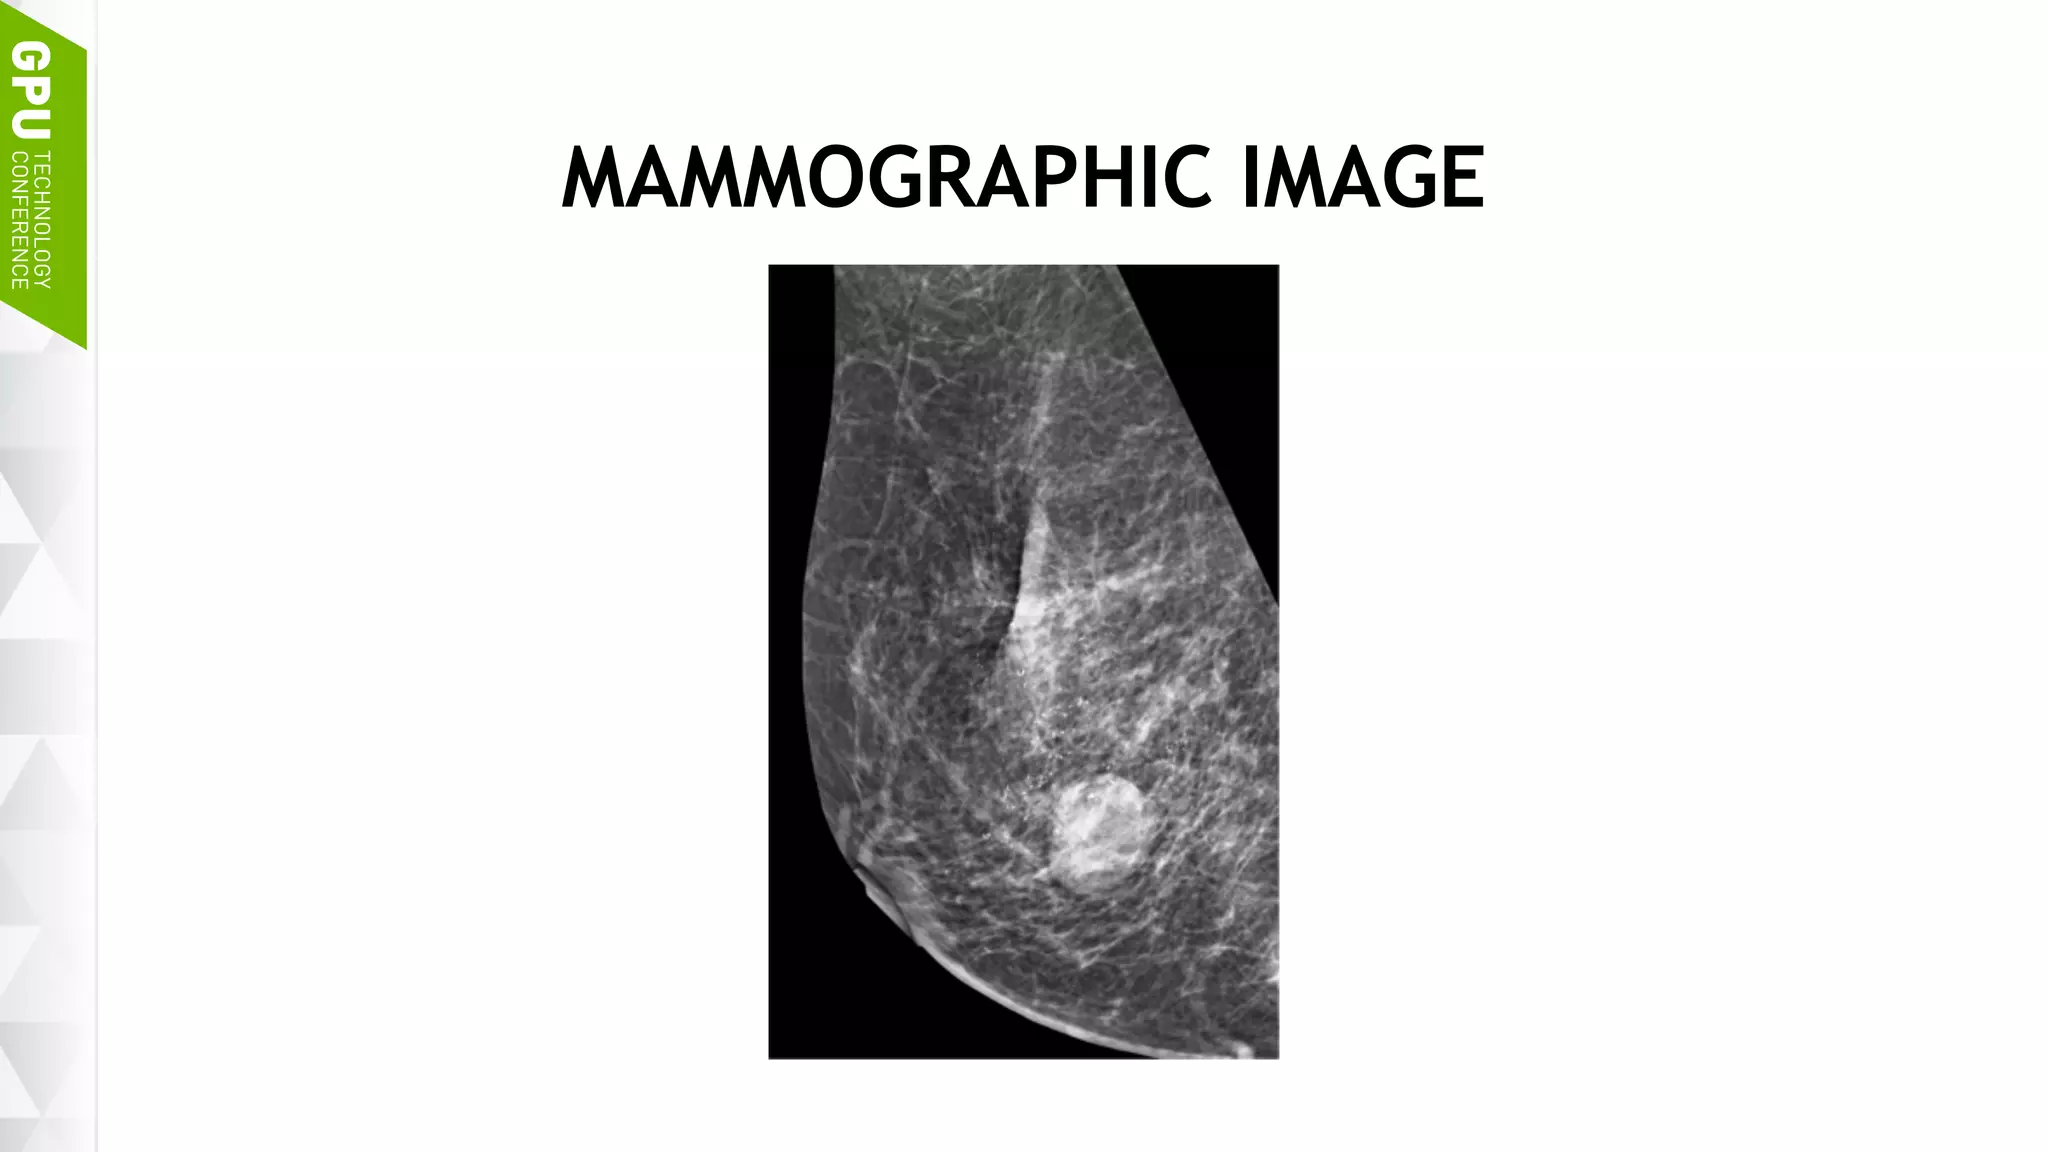

MAMMOGRAPHIC IMAGE